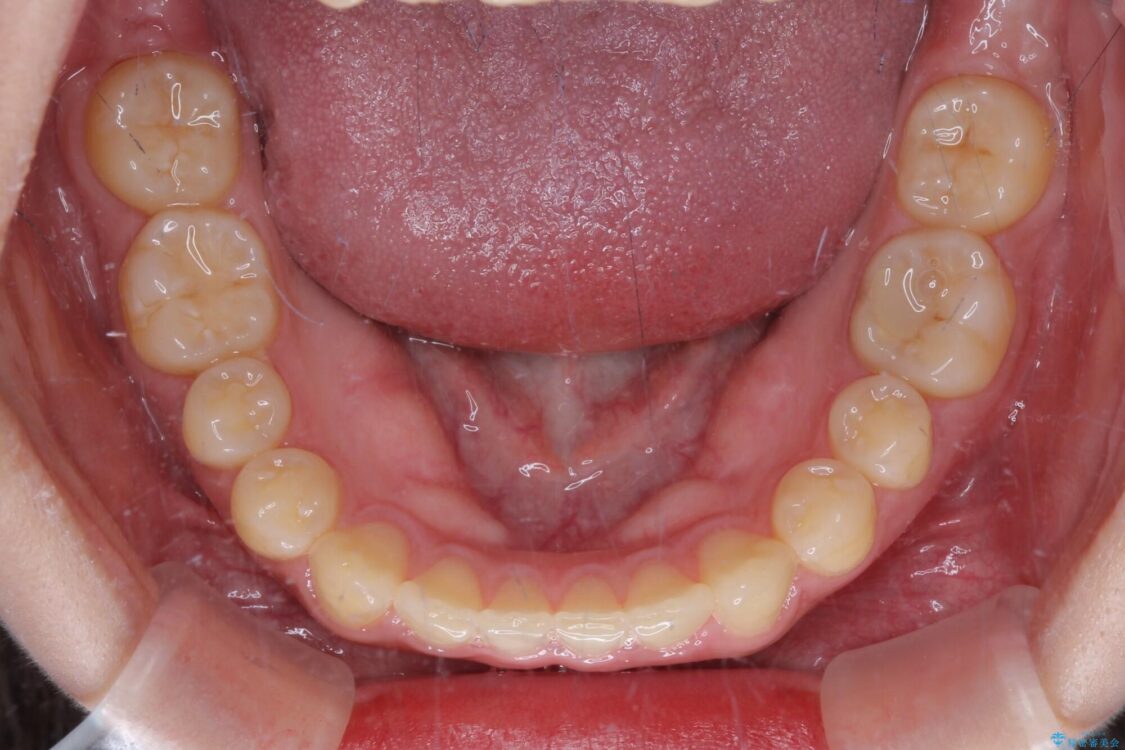

治療後

• 治療途中の奥歯と矯正治療の後戻り インビザライン・ライトによる矯正治療 治療後画像